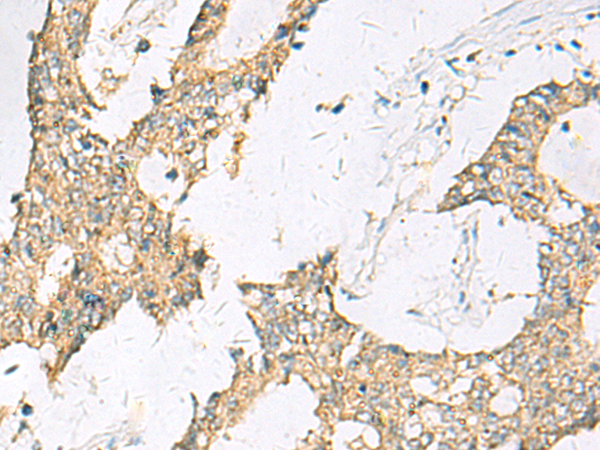

分类: 科研抗体货号: P10356别名: SAMP32应用: IHC反应种属: Human